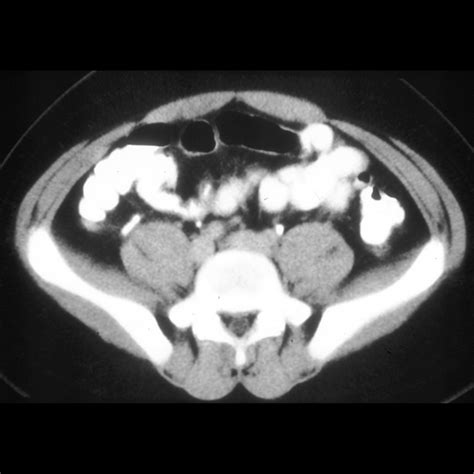

When patients present with abdominal pain—particularly in the lower right quadrant—medical professionals must quickly determine if the appendix is inflamed, a condition known as appendicitis. The primary diagnostic tool used in this process is imaging (ultrasound, CT scan, or MRI). By measuring the normal appendix size against current imaging, radiologists can identify inflammation, as an inflamed appendix will almost always appear enlarged due to swelling and fluid accumulation.

Typically, a normal appendix size is defined by a maximum outer diameter of 6 millimeters or less when measured on a cross-sectional image. If the diameter measures above 6 millimeters, clinicians become concerned about potential appendicitis, especially if other clinical symptoms are present.

First, the imaging modality plays a significant role. CT scans are generally considered the gold standard for visualizing the appendix because they provide high-resolution, cross-sectional views. Ultrasounds are often used, especially in children or pregnant individuals to avoid radiation, but they can be limited by bowel gas or the patient's body habitus, making it harder to obtain an accurate measurement of the normal appendix size.